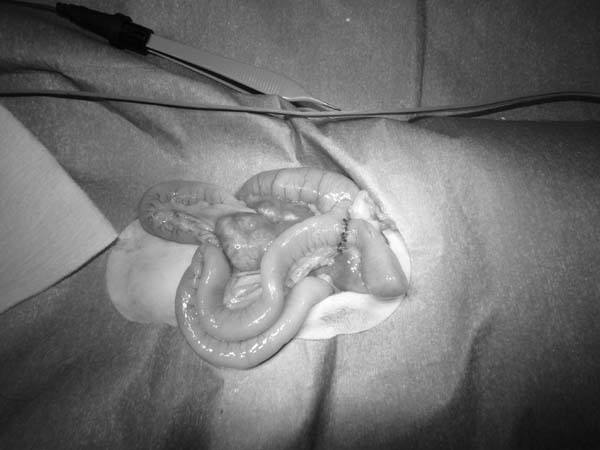

ワンちゃんが乳腺にできた複数のシコリを気にされて来院されました。bilateral mastectomyで対応しました。摘出後の病理組織検査の結果は、「R3-4間腫瘤:乳腺癌(複合型)」でそれ以外は「良性乳腺混合腫瘍」でした。無事元気に退院し、その後再発もなく経過は良好です。よかったね。